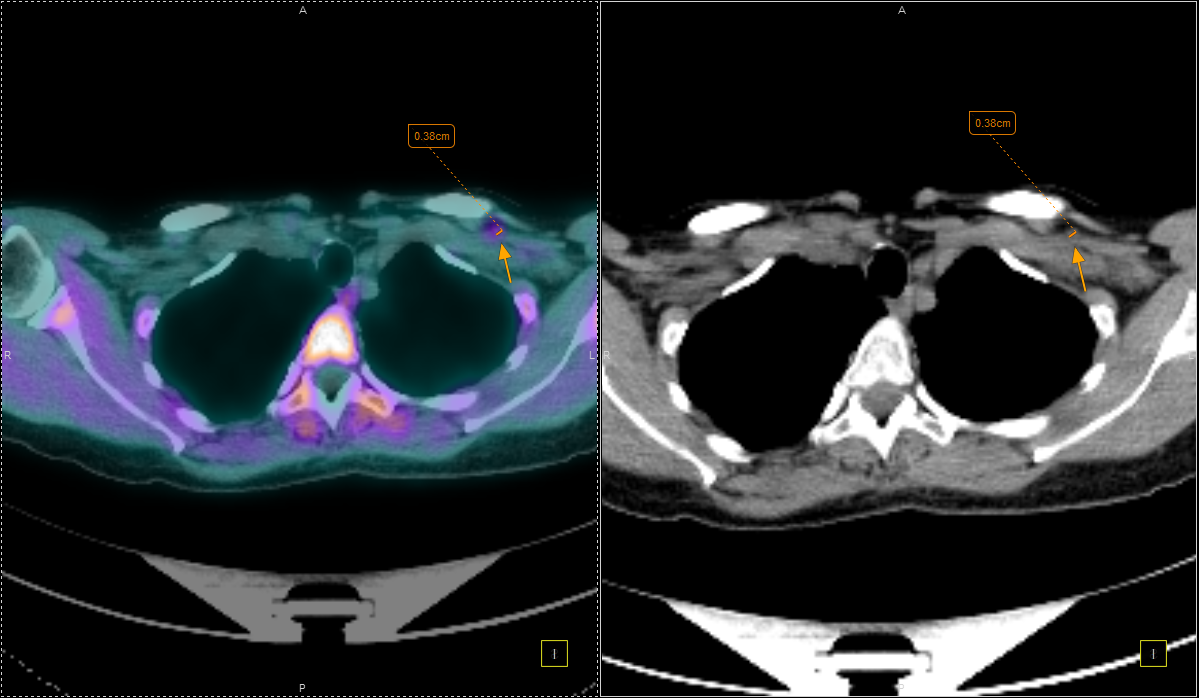

Στην ογκολογία, η PET/CT συμβάλλει με εξαιρετική ακρίβεια:

Ιδιαίτερα σημαντική είναι η χρήση των δεδομένων της PET/CT από το Κέντρο Ακτινοθεραπευτικής Ογκολογίας, για τον ακριβή σχεδιασμό της ακτινοθεραπείας, με στόχο την επίτευξη του καλύτερου θεραπευτικού αποτελέσματος και τη μικρότερη δυνατή ακτινική επιβάρυνση των υγιών ιστών.

Με τη χρήση ειδικού λογισμικού Τεχνητής Νοημοσύνης (MIM – Lesion ID) πραγματοποιείται αυτόματος υπολογισμός της έκτασης και του όγκου των θέσεων ενεργού νόσου. Ξεπερνώντας τις δυνατότητες του ανθρώπινου οφθαλμού υπολογίζεται το συνολικό φορτίο νόσου πριν και μετά την θεραπεία επιτρέποντας ακριβέστερο χειρισμό του ασθενούς από τον θεράποντα ιατρό.